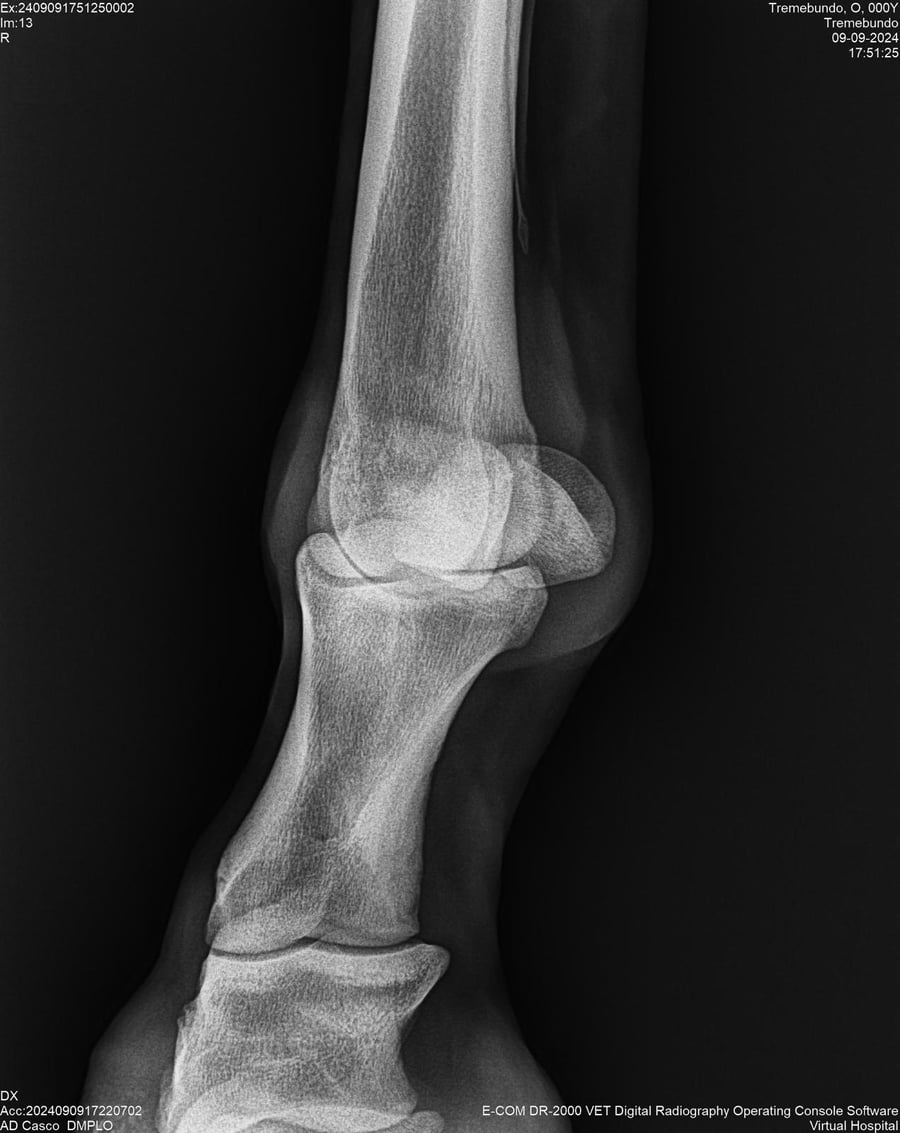

LOTE 37, TREMEBUNDO

Identificador: #291140-

Generacion 2022